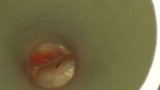

Bogata w płytki i leukocyty fibryna jest stosowana w regeneracji tkanek od ponad 15 lat. Pozytywny wpływ PRF (platelet-rich fibrin) na regenerację tkanek miękkich jest niewątpliwy, bezsporny i częściowo udowodniony w badaniach klinicznych i analizach biochemicznych. Wpływ PRF na regenerację tkanki kostnej jest obserwowany klinicznie, ale nadal niedostatecznie poznany jest mechanizm tego zjawiska.

Platelet- and leukocyte-rich-fibrin has been used in regeneration of tissue for more than 15 years. The positive influence of PRF on the regeneration of soft tissue is undoubtedly, without question and partially proven in clinical studies and biochemical analysis. Influence of PRF on regeneration of bone tissue is observed clinically but the mechanism of this phenomenon is still not sufficiently known.